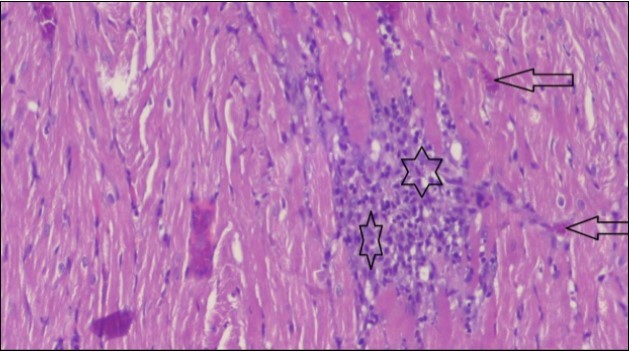

An important organ that is affected directly by the obesity which is the heart: The heart is the main important organ in circulatory system, the heart wall has three basic layers; the tunica intima of the heart is called endocardium, the tunica media of the heart is called the myocardium, the tunica adventitia of the heart the epicardium. The histological examination of the hearts of control rats feeding standard diet showing normal cardiac tissue with elongated, unbranched multinucleated muscle fibers (arrow), (Figure 1). The rats are feeding (HFD) for 2 weeks (obese rats) showing large number of inflammatory cells (star), degeneration muscles fiber ,circle and congested Blood vessels (arrow) (Figure 2). By comparison hearts of rats are treated by fennel after obesity and control rats observed show improved cardiac tissue with less infiltration (star) and well organized elongated muscle fibers with peripheral nuclei (arrow) (Figure 3). While examination of rats heart that treated by ator after obesity appears show less improved cardiac tissue with few inflammatory cells between disorganized muscle fiber (star), (Figure 4). While combined hearts of rats are treated by fennel and ator after obesity and control mice are showing nearly cardiac tissue with well-organized muscles fibers (arrow), (Figure 5).

Figure 1.Photomicrograph of heart section of control rat showing normal cardiac tissue with elongated, un branched multinucleated muscle fibers (arrow), (H&E) (400X).

Figure 2.Photomicrograph of heart section of an obese rat showing large number of inflammatory cells (star), degeneration muscles fiber, circle and congested Blood vessels (arrow), (H&E) (400X).

These results were confirmed with histological changes of feeding rats heart tissues with high fat diet only, which showed vaculation of tunica media and narrowing in the lumen of aorta sections as well as congestion of cardiac blood vessel and hyalinosis of its wall. This result was confirmed by Szilvassy et al., 78, who indicated that although hyperlipidemia increases oxidative stress in the cardiovascular system, it renders the heart and the vasculature more susceptible to stress. Ouwens et al. 79 identified that development of hyper-cholestremia, which is one of the risk factors for cardio vascular diseases is associated with increased blood levels of TC, LDL-C and VLDL-C as well as lowered levels of HDL in rats fed on high fat-diet. This result was confirmed by histological study, which revealed apparent normal histological structure of heart in all treated rats with fennel seeds. Epidemiologic studies have shown an inverse correlation between HDL-C level and the risk of cardiovascular disease. Increasing the HDL cholesterol level by 1mg may reduce the risk of cardiovascular disease by 2 to 3 percent 80. The present data agreed with Fatiha et al. 81, who reported that hyper-lipidemic rats treated with fennel extract had significant decrease in plasma levels of TL, TG, TC, LDL-C and VLDL, and significant increase in HDL-C level. The current study demonstrates that the alteration induced by high fat diet causing changes in blood parameters. These changes are exhibited through a decrease in RBCs, Ht, Hb and platelet and these changes could be due to oxidative stress, which lead to lipid peroxidation in RBCs membranes, auto oxidation of hemoglobin. As regards the total WBCs, lymphocytes and monocytes showed a marked decrease. While a distinct increase in the percentage of neutrophils and esinophils. The present, demonstrates that rats treated with (fennel), (ator) and (fennel with ator) exposure provided significant protection to the altered haematological variables. The effect of the treatment with fennel and ator is more effective than fennel only or ator only. The current study showed that the serum levels of the total protein and albumin in the obese group were significantly higher than those of the control group. The administration of (fennel) revealed significant decrease in the serum levels of the albumin and total protein as compared to the obesity group, although the serum levels of the albumin and total protein of the Ator group less than the obesity group. Otherwise, the levels of the total protein and albumin in fennel and Ator group were near to the similar value of the control group. The finding of this study indicates that the concentration of Malondialdehyde (MDA) and Myeloperoxidase (MPO) in liver homogenates of the fennel and ator group significant decrease than group (3) and group (4) and obesity group. There is a growing awareness that obesity is a prime risk factor for the development of dyslipidemia profile and that oxidative stress may play a role in various adverse effects of obesity.